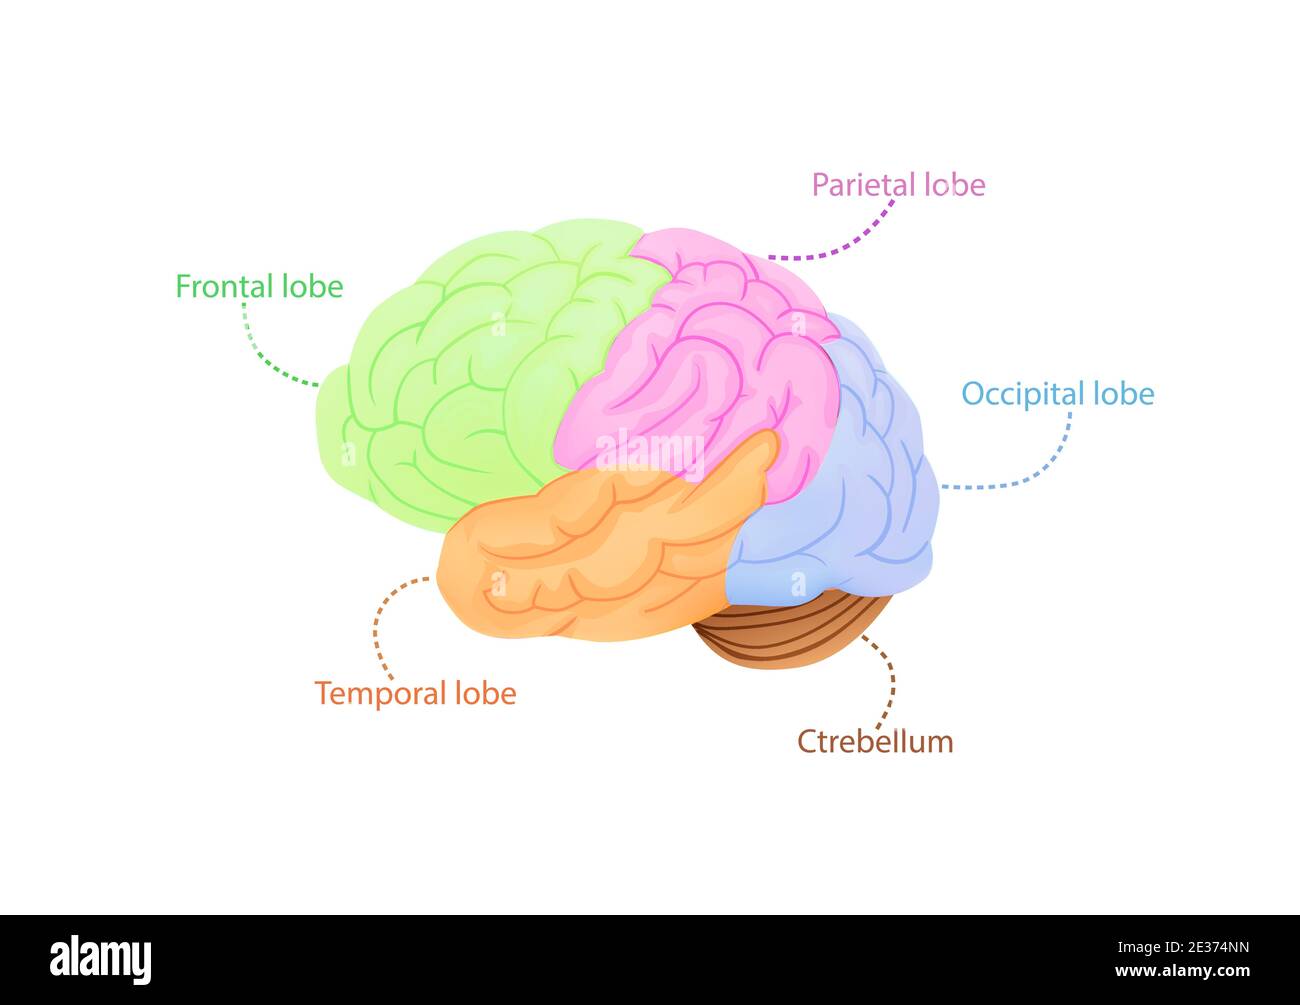

RF2E374NN–Struttura dell'illustrazione della corteccia cerebrale. Regioni anatomiche colorate responsabili dell'intelligenza e del movimento.